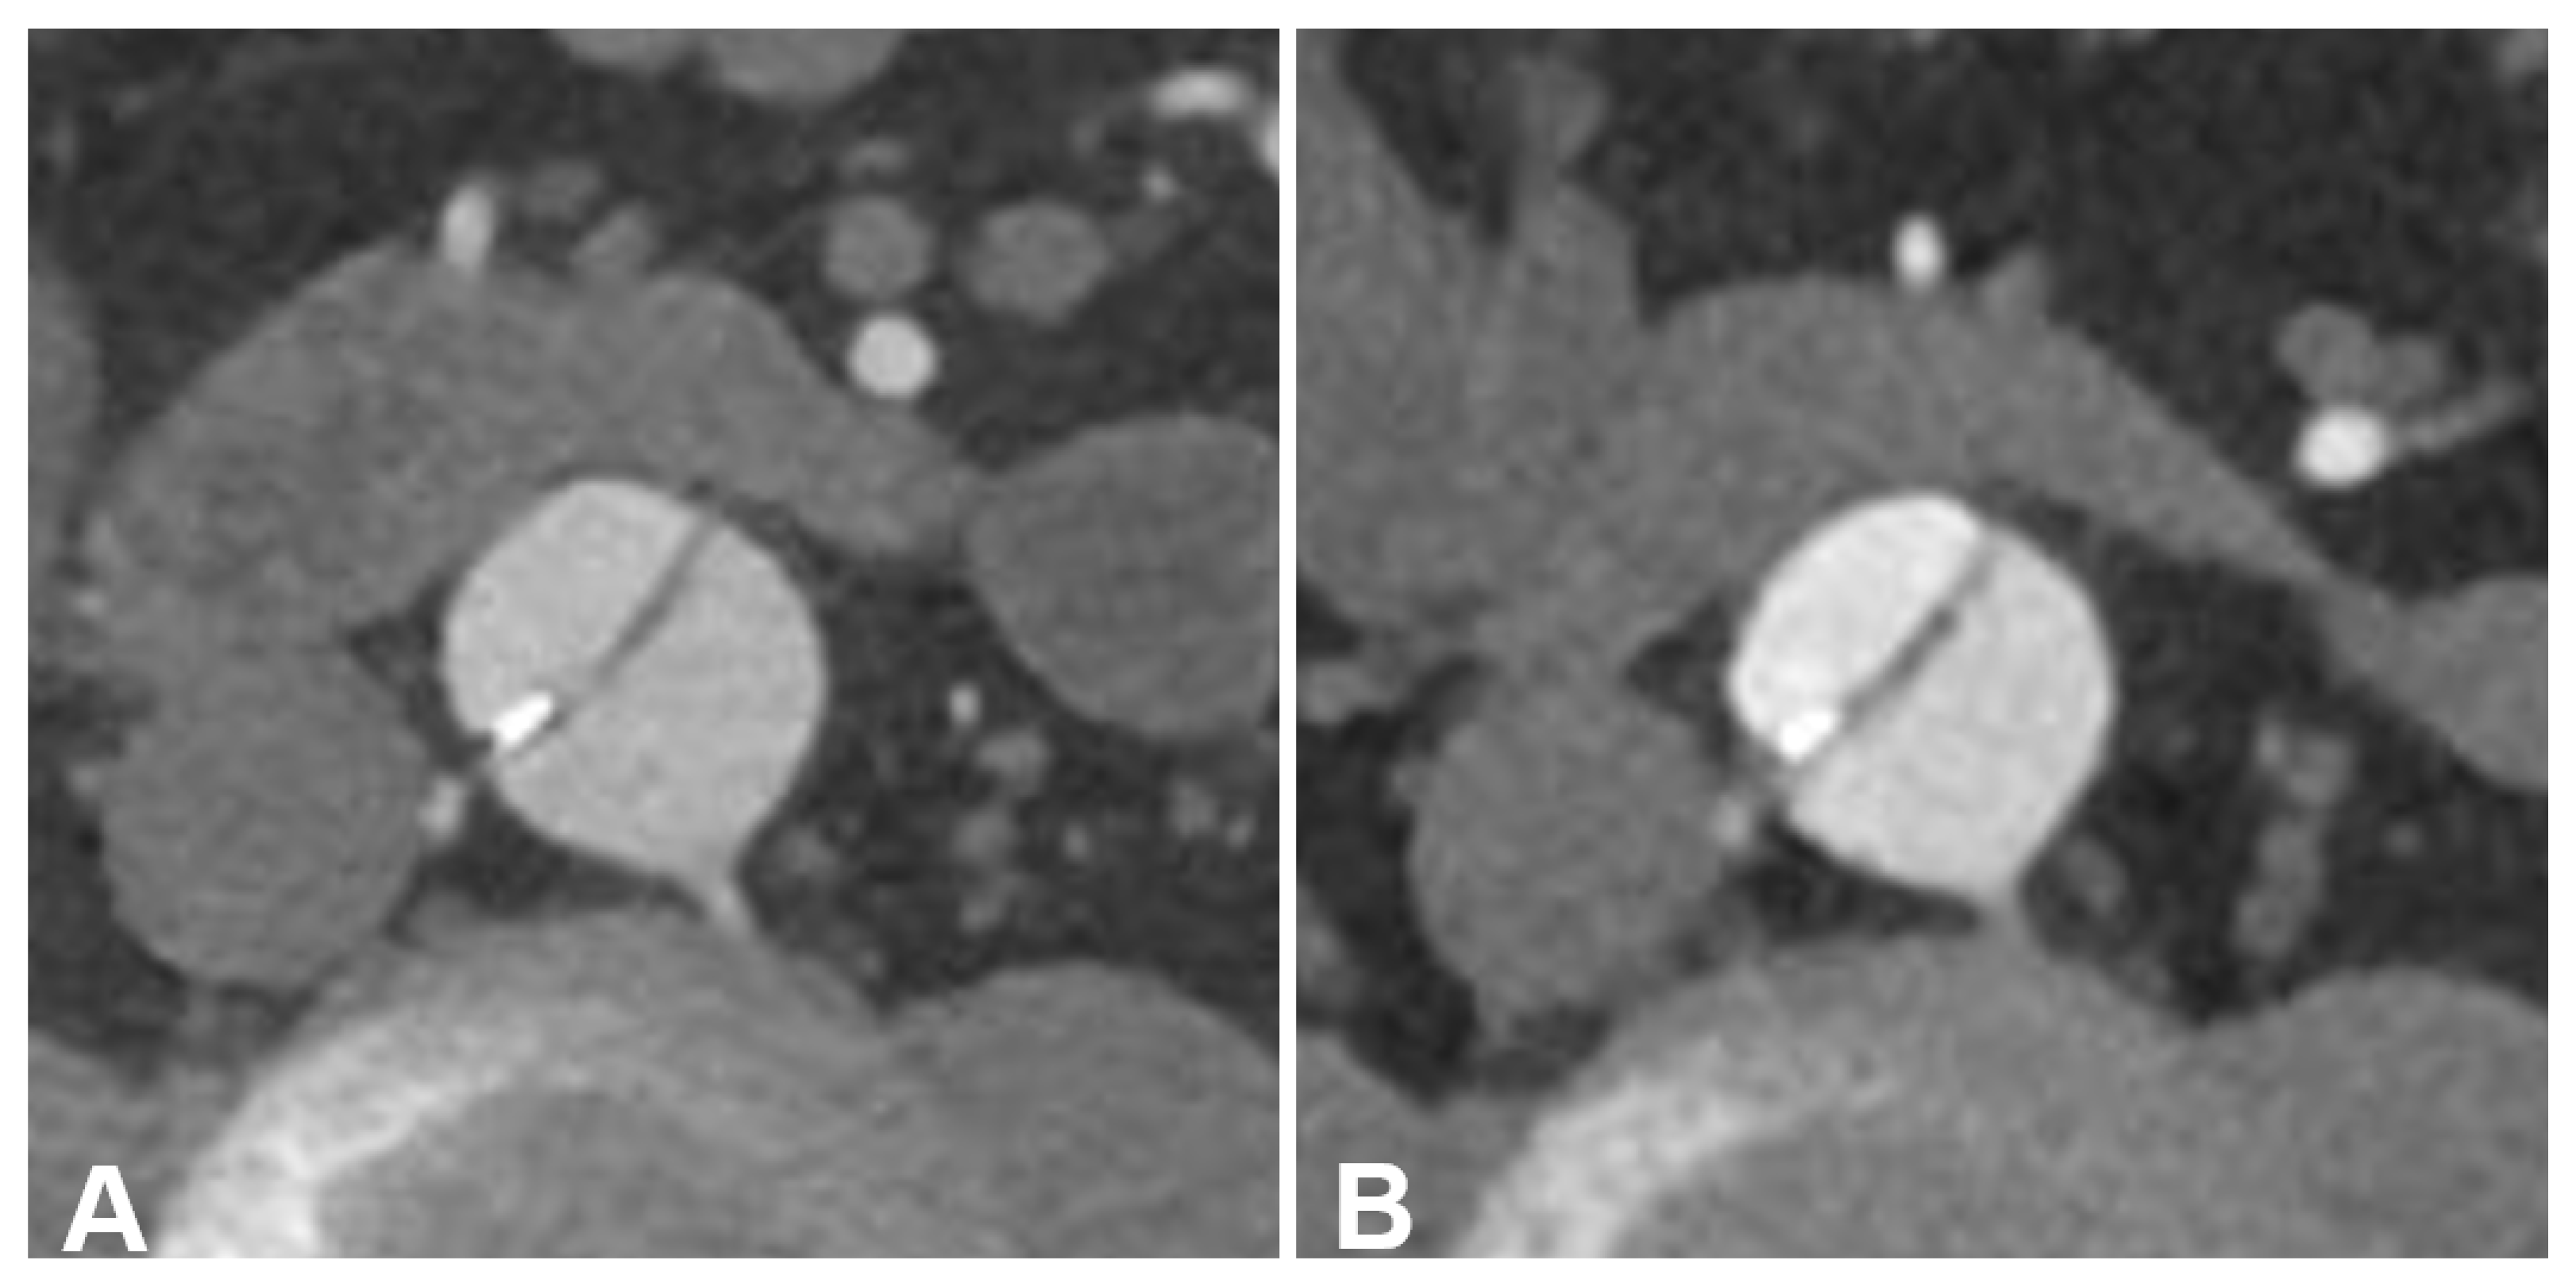

Figure 6.

Side-by-side comparison between energy-integrating detector computed tomography (EID-CT) (A) and photon-counting detector CT (PCD-CT) angiography (B) in a 56-year-old man with TEVAR. EID-CT: CTDIVol 5.73 mGy; SSDE 6.42 mGy. PCD-CT: CTDIVol 5.72 mGy; SSDE 6.39 mGy. Representative axial orientated CTA images (reconstruction kernel Bv36; slice thickness/increment 3 mm; window setting: width 700 HU/center 100 HU). (A) EID-CT with subjective advantages in terms of blooming/beam hardening (compare wall calcification in the dissection membrane) and vessel sharpness (see dissection membrane). (B) PCD-CT with advantages in terms of luminal contrast and overall image quality.